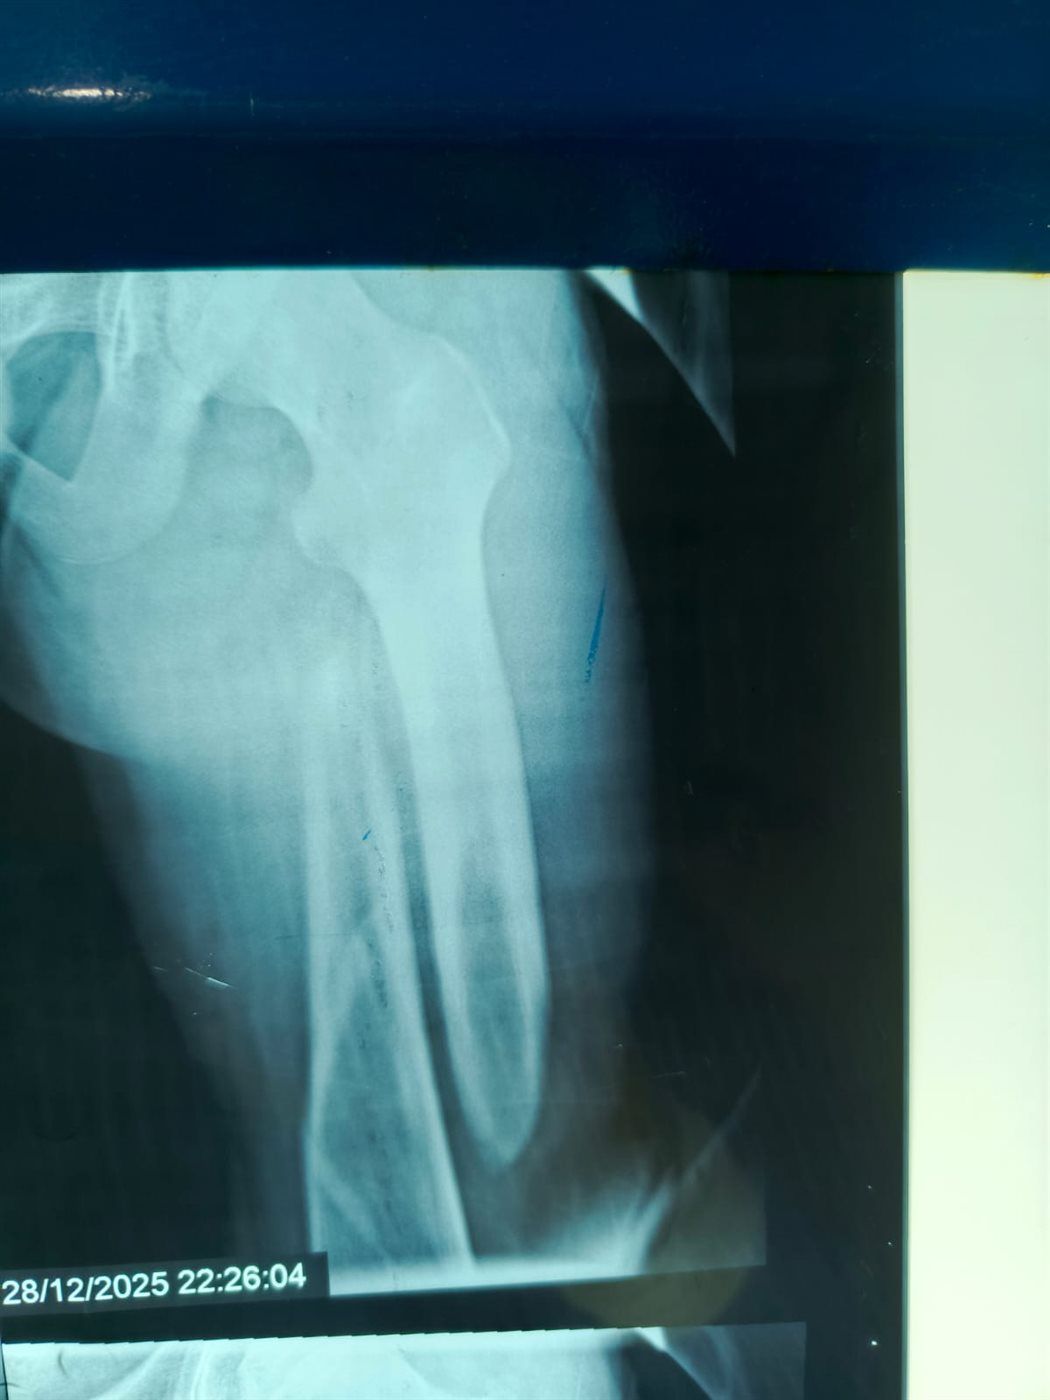

نجح الفريق الطبي بقسم الطوارئ والعمليات بمستشفى مغاغة العام بمحافظة المنيا، في إنقاذ شاب يبلغ من العمر 16 عامًا، تعرض لحادث مروري مروع أسفر عن كسر مفتت متعدد المواضع بعظمة الفخذ الأيسر، وذلك من خلال إجراء جراحة متقدمة باستخدام تقنية المسمار النخاعي التشابكي في زمن قياسي.

وفور وصول المصاب إلى قسم الطوارئ، جرى التعامل الفوري معه، وتم اتخاذ القرار الطبي العاجل بإجراء جراحة المسمار النخاعي التشابكي دون فتح موضع الكسر، بما يتوافق مع أحدث البروتوكولات الطبية العالمية. واستغرقت العملية نحو ساعتين ونصف فقط، غادر بعدها المريض غرفة العمليات في حالة مستقرة.

وتميزت الجراحة بعدة مزايا، من بينها: جروح جراحية محدودة للغاية، وتقليل فرص النزيف والعدوى إلى أدنى حد، وتسريع معدلات التئام العظام مقارنة بالطرق التقليدية.